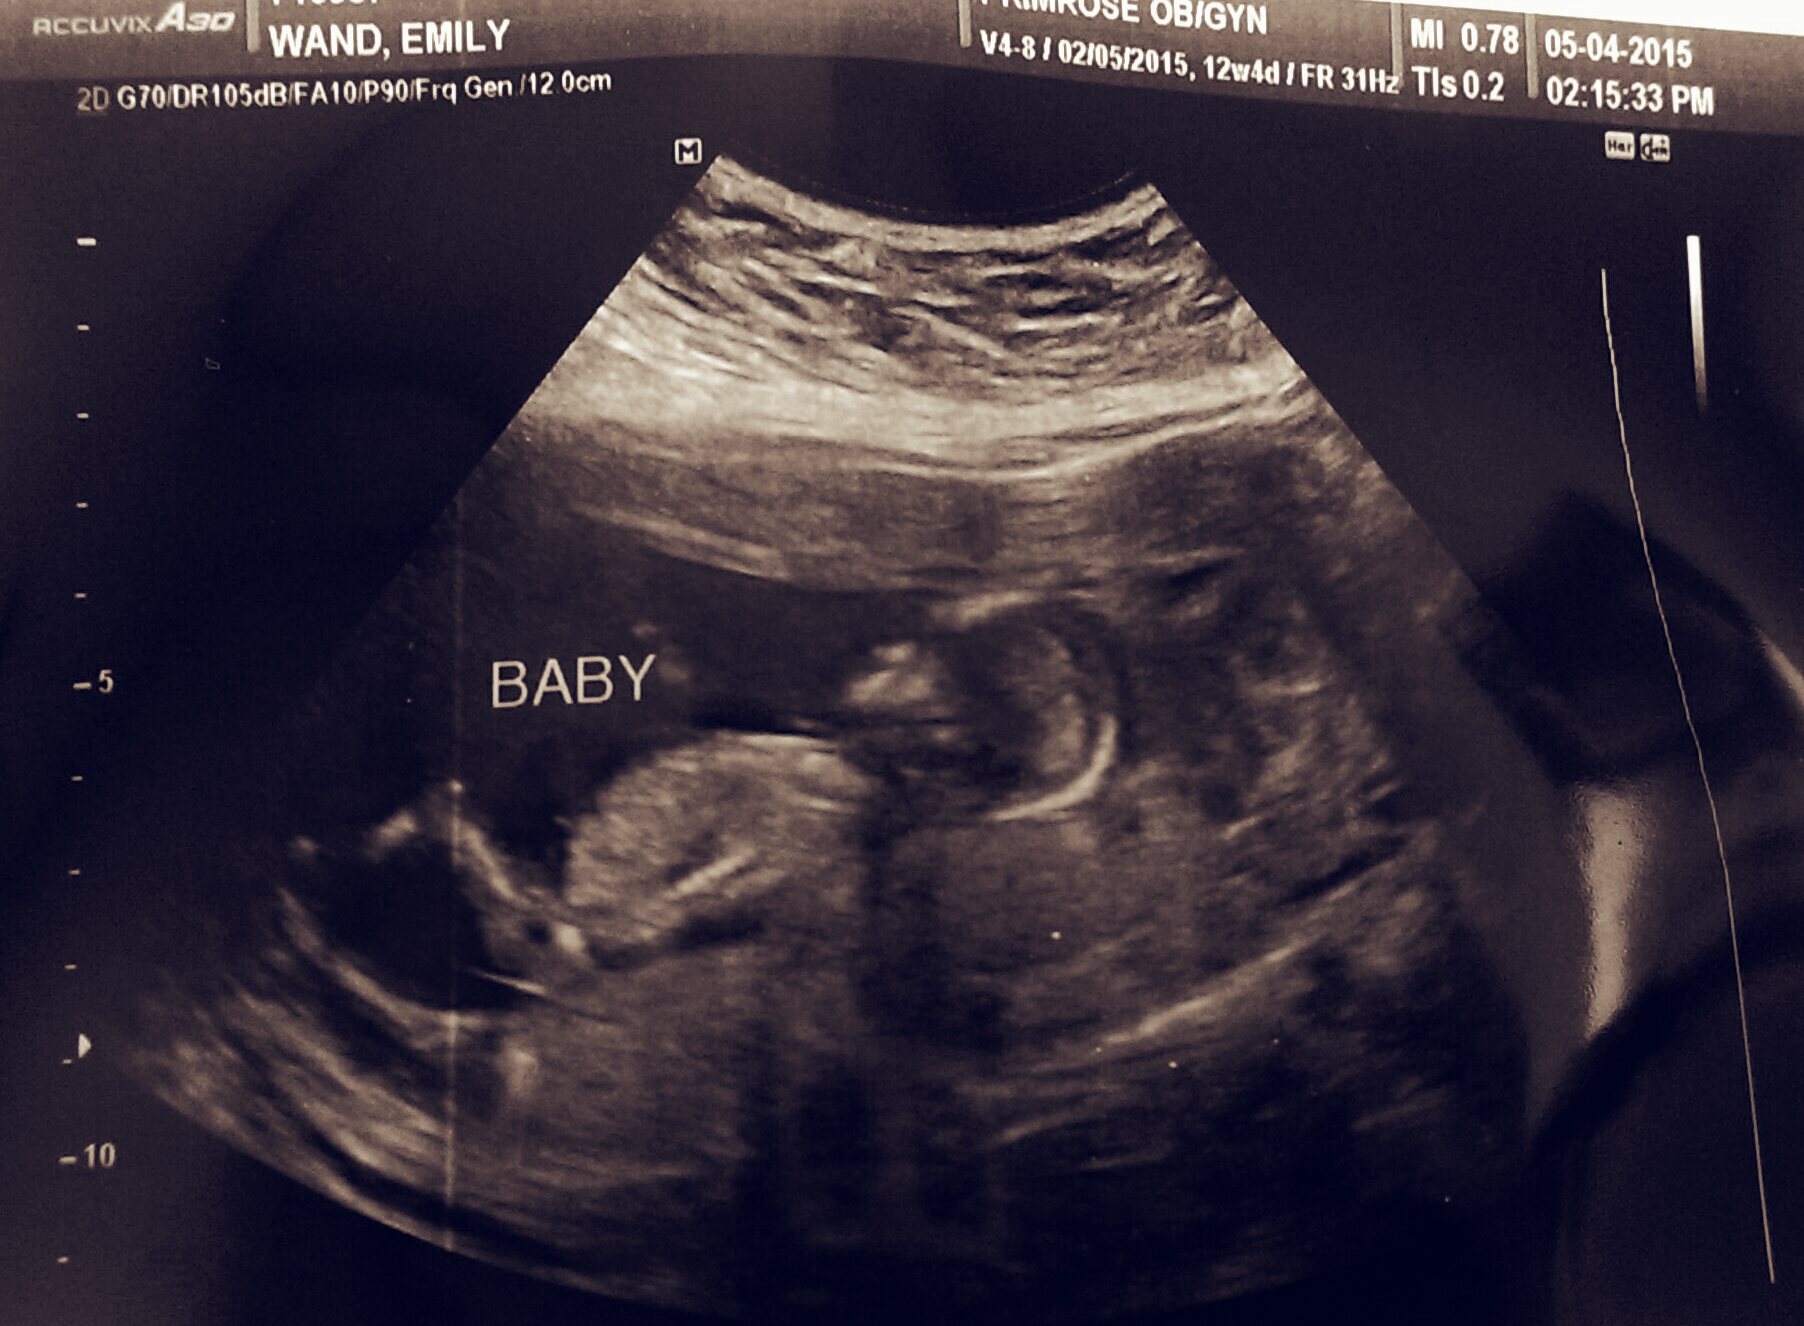

@emily.jeanne the appointment went well! Heard the baby's heartbeat! Baby was hiding behind one of my main arteries, so it was hard to distinguish between my heart beat and hers. As for the SCH, I have to wait until May 11th to find out if we are in the clear ( ultrasound results ) they told me yesterday it is very small at 1cmx1.8cm ! That was a relief! Although we are still on the same restrictions, no exercise, no sex, and no heavy lifting. Did you other momma's find out the size of your SCH ?

Had my ultrasound today... She couldn't find the blood clot! But she did find a healthy active baby with a heart beat of 166bpm. The GA is 12w5d instead of 12w2d... Very happy!

@emily.jeanne glad baby is ok! How did your U/S look? We had our NT testing yesterday and the ultrasound tech said she couldn't find the SCH. But when I look at my picture it looks like a SCH underneath baby.... I have to wait for a week to see the OBGYN. what did your ladies look like and what do you think ?

@amandaejgreen I think that is way too close to baby to be a SCH, I think it's just fluid behind it's back. You can see mine is the thin black line under the baby's rump almost at the edge of the picture.